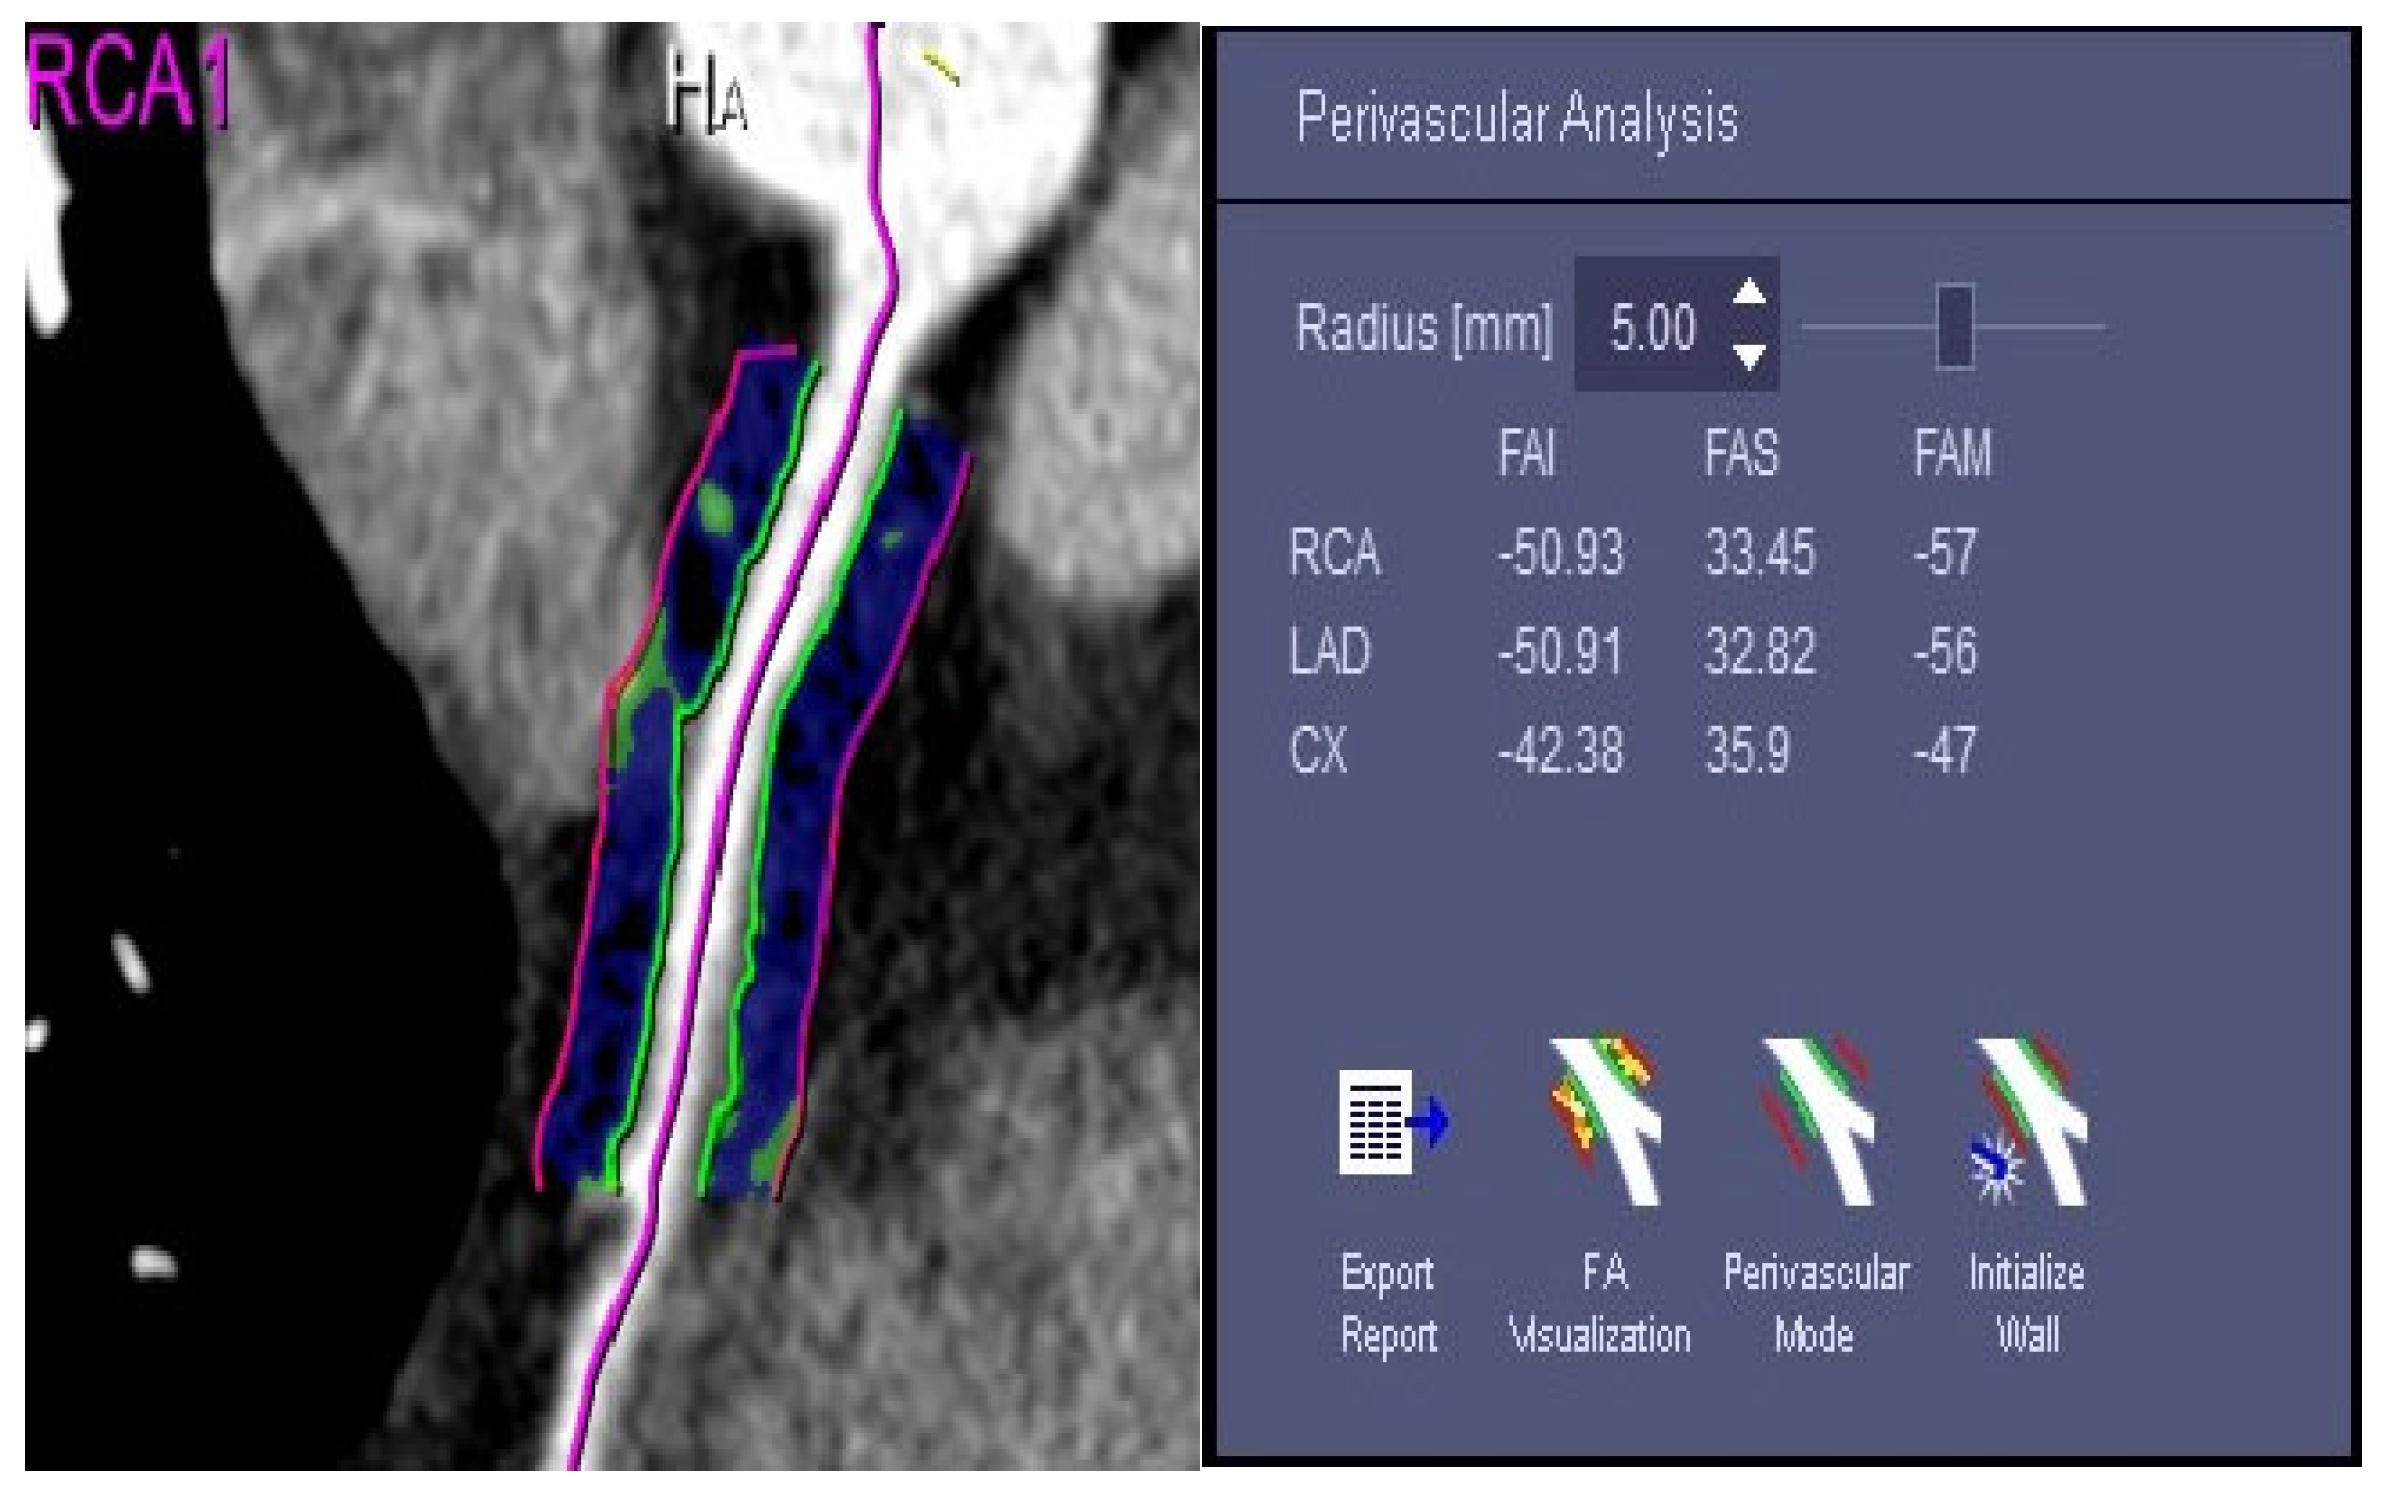

2.5. Measurement of the FAI Value of Fat around the Coronary Artery